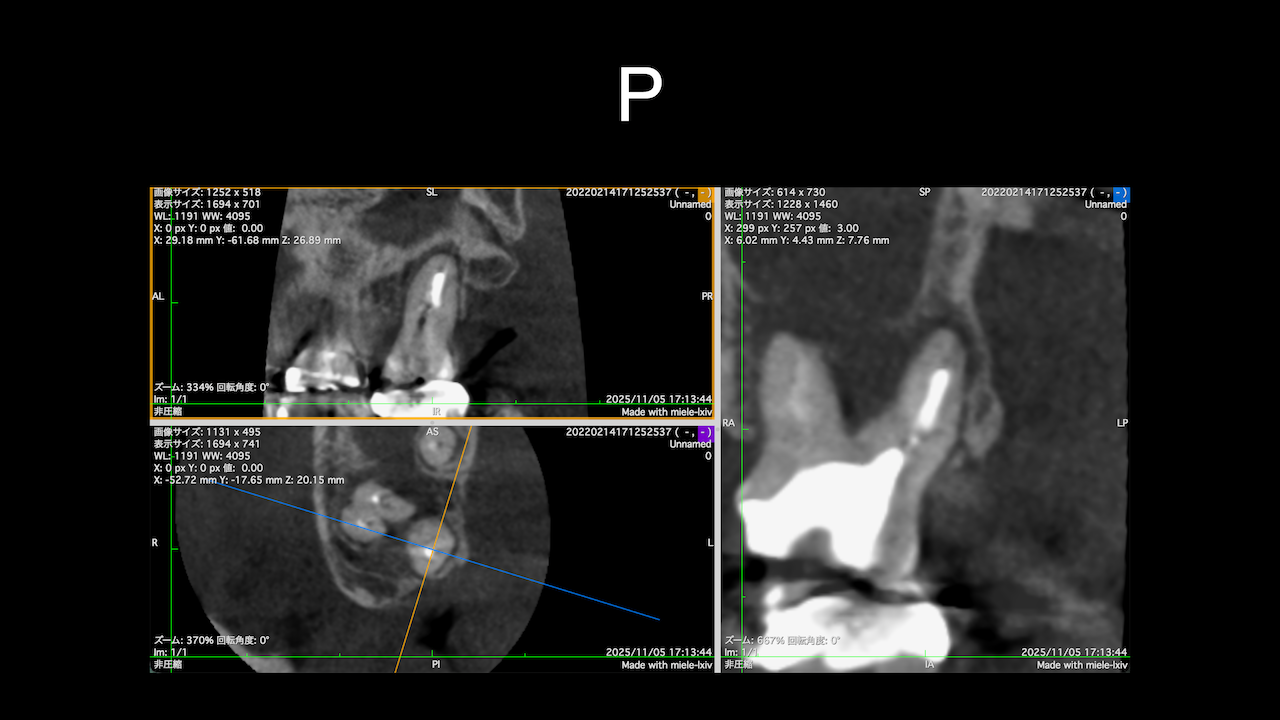

Sinus tractがある歯牙の再根管治療だ。

DB根はすでに切断されている。

が、逆根充がなされていない。

DBは根切済みだ。

Pにも病変がある。

ということは、再根管治療だろう。

ただ、予後はGuardedだ。

なぜか?根切がうまく行っていないからだ。

臨床的にDB

この後、

Sinus tractは消失した。

3ヶ月経過した。

DBの病変が小さくなっている。

Pは病変が大きくなっていうように見えるがまだわからない。